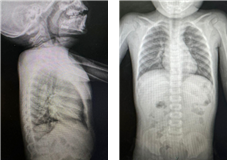

Male preschool patient, 2 years 8 months old, without associated perinatal pathologies, optimal growth and development for the current age. It has a surgical history of ileocecolic intestinal invagination at 7 months requiring ileostomy type of intestinal derivation with subsequent reinstallation at 4 months of the initial surgery. Rest of the background without relevance to the case. Patient is received at the pediatric emergency service of the Civil Hospital of Guadalajara Fray Antonio Alcalde secondary to the intake of alkaline substance (caustic soda) in bulk. By indirect interrogation to the mother, the patient accidentally ingested the substance on January 14, 2024 at approximately 11:00 a.m., presenting two vomiting of gastro-food content 5 minutes after the ingestion.1 Go immediately to the pediatric emergency service, the patient is received irritable but with an adequate hemodynamic state, without pathological data of commitment at the respiratory level (Figure 1).

Figure 1 Physical examination.

Physical examination presents TA 90/64 mmHg, FC 86 lpm, FR 18 rpm, oxygen saturation of 96%. Adequate state of alert, presence of edema in the perioral mucosa in addition to significant sialorrhea, cardiopulmonary auscultation without presenting pathological findings, rest of the examination without any abnormality. Chest x-ray is performed in AP and lateral projection where there is no evidence of mediastinitis or any type of infiltrate at the level of the pulmonary parenchyma.